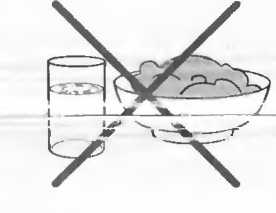

Подготовка

1. Подготовка